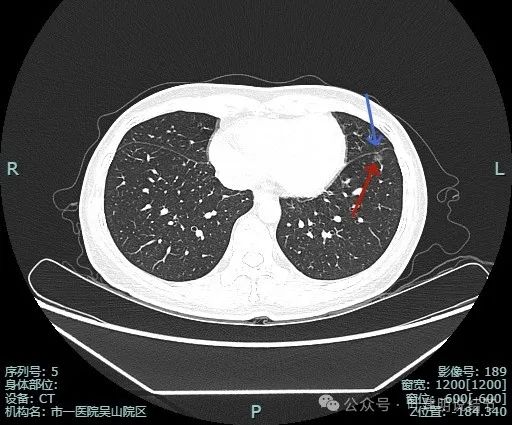

靶重建图像:

病灶边缘毛糙,微小血管进入明显。灶内密度略不均。

血管进入与穿行明显,而且在病灶内有发出血管分支,病灶表面不平,有毛刺征。

小血管进入明显,边缘有毛刺征,整体轮廓与边界清。

血管进入,灶内小空泡征,邻近细支气管有扩张,表面有细毛刺。